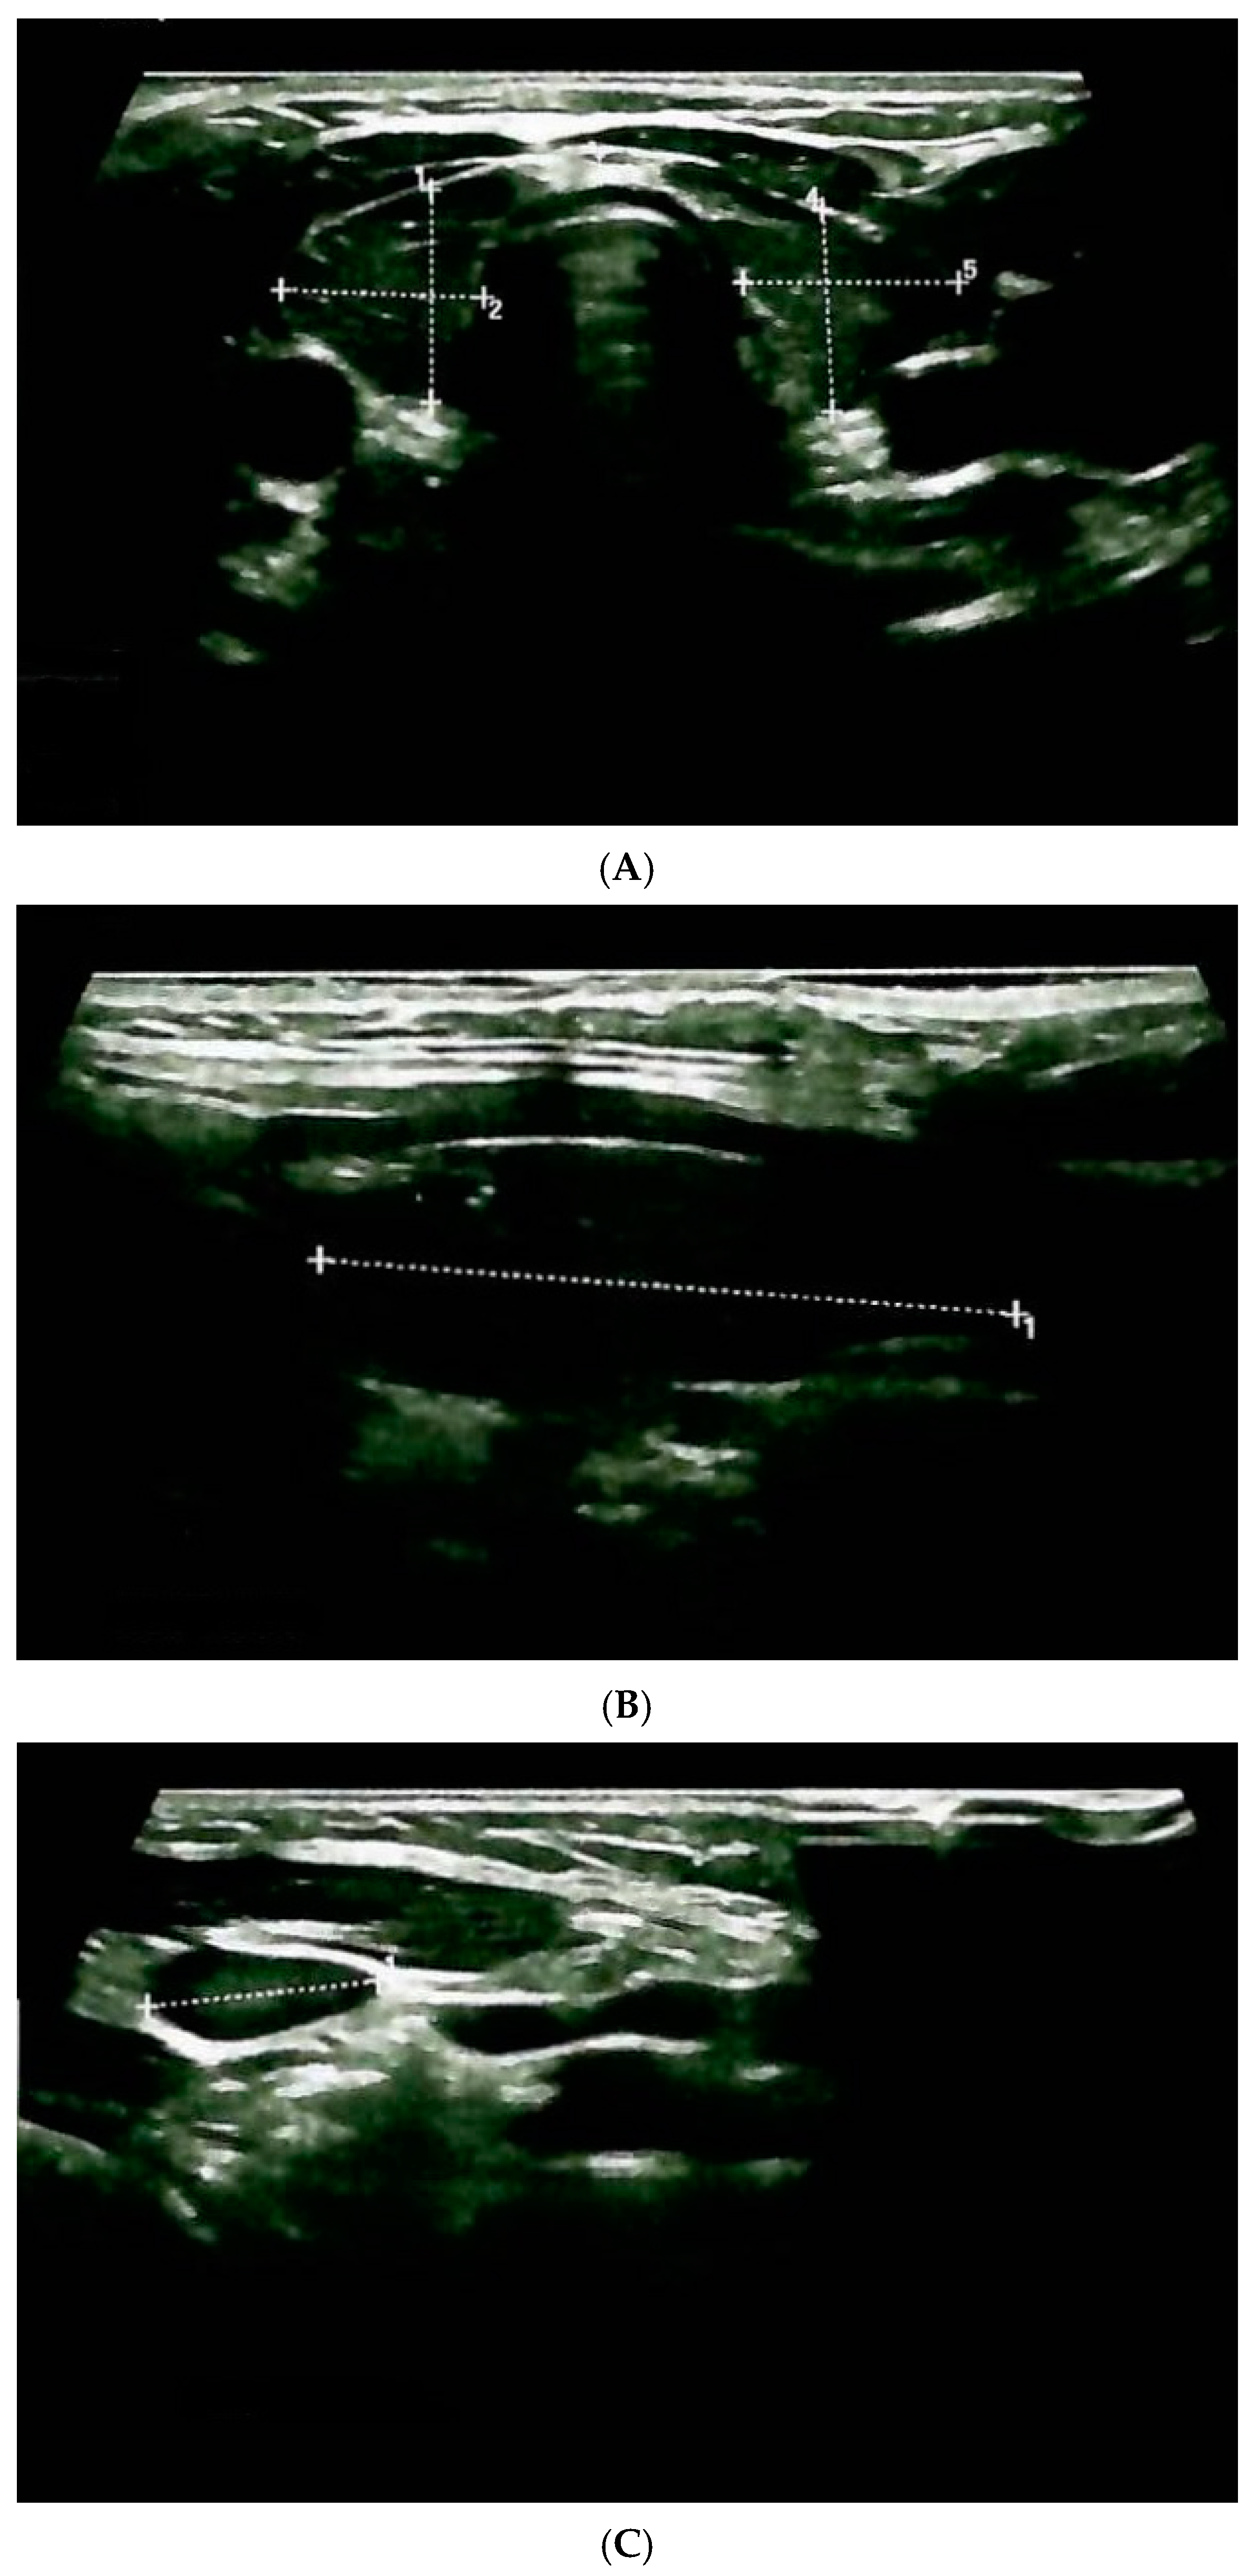

2.1. Admission of the Pediatric Case

| Age at diagnosis | 6 years (RET genetic testing within the first year of life) | ||

| Surgery | Recommended (planned) | ||

| Current hormonal status | Calcitonin = 10.4 ng/mL (normal: 1–4.8) | Plasma metanephrines = 40 pg/mL (normal: 0–90) Plasma normetanephrines = 42 pg/mL (normal: 20–200) | PTH = 42 pg/mL (normal: 15–65) Total serum calcium = 9.45 mg/dL (normal: 8.4–10.2) |